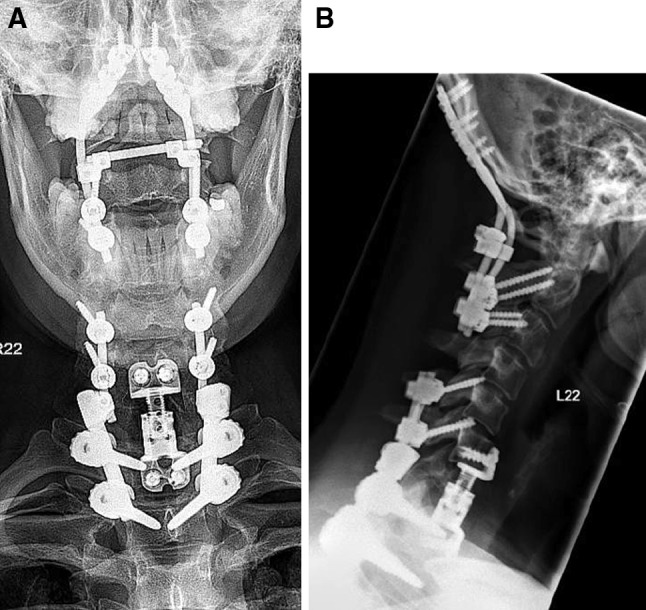

Because of the neurological deficit, immediate surgery was performed with decompression of the right C7 foramen and posterior stabilization from C5 to Th2 and fusion from C6 to Th1. Postoperatively, patient regained complete neurological function. 4 days later, anterior corpectomy of C7 and fusion from C6 to T1 was performed using a plate-cage construct. After anterior surgery, patient was turned around and posterior reduction and stabilization of the occipital condyle fracture from C0 to C3 was performed.

Patient was operated in a prone position with the head fixed in a Mayfield clamp. After midline incision and dissection of the neck muscles, bony elements from the occiput to C3 were exposed. Care was taken not to violate the facet joints and bone cortex. The following steps were performed under lateral image intensifier control: drilling and inserting of self-tapping lateral mass screws into C3 and short isthmus screws into C2 (Axon, Synthes, Oberdorf, Switzerland); drilling and inserting of self-tapping screws into the occiput to fixate the occiput rods (OCF, Synthes, Oberdorf, Switzerland). To reduce the rotational misalignment, the head (C0/1) was rotated approximately 20° to the right by adjusting the Mayfield clamp. Furthermore, the C2/3 complex was rotated to the left under visual control until the spine looked straight. The construct was fixed and a cross-link was mounted. Radiological images were taken in antero-posterior and lateral view to confirm anatomical reduction. No bone grafting was performed. No intra or postoperative complication was noted (Fig. 4).

Fig. 4.

Postoperative X-rays after open, indirect reduction and temporary C0–3 stabilization and decompression and stabilization C5–T2 with fusion C6–T1